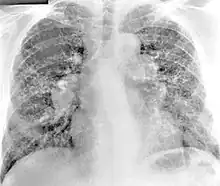

| Peribronchal non-necrotizing granuloma from berylliosis | |

Chest radiography findings of berylliosis are non-specific. Early in the disease radiography findings are usually normal. In later stages interstitial fibrosis, pleural irregularities, hilar lymphadenopathy and ground-glass opacities have been reported.[20][21] Findings on CT are also not specific to berylliosis. Findings that are common in CT scans of people with berylliosis include parenchymal nodules in early stages. One study found that ground-glass opacities were more commonly seen on CT scan in berylliosis than in sarcoidosis. In later stages hilar lymphadenopathy, interstitial pulmonary fibrosis and pleural thickening.[21]